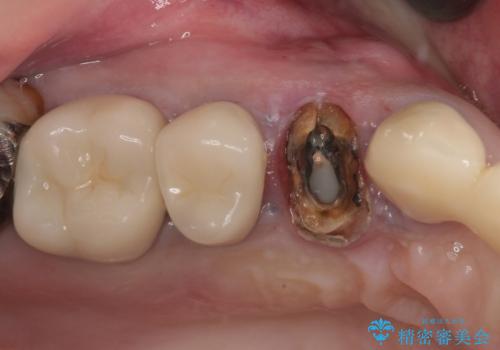

- 歯肉から膿が出てくるのが気になるとのことで来院された患者様です。

診察したところ、歯根に破折線が確認され抜歯が必要な状態でした。

歯肉や歯槽骨の状態は良好であったため、抜歯即時埋入インプラントによる補綴治療を行うこととしました。